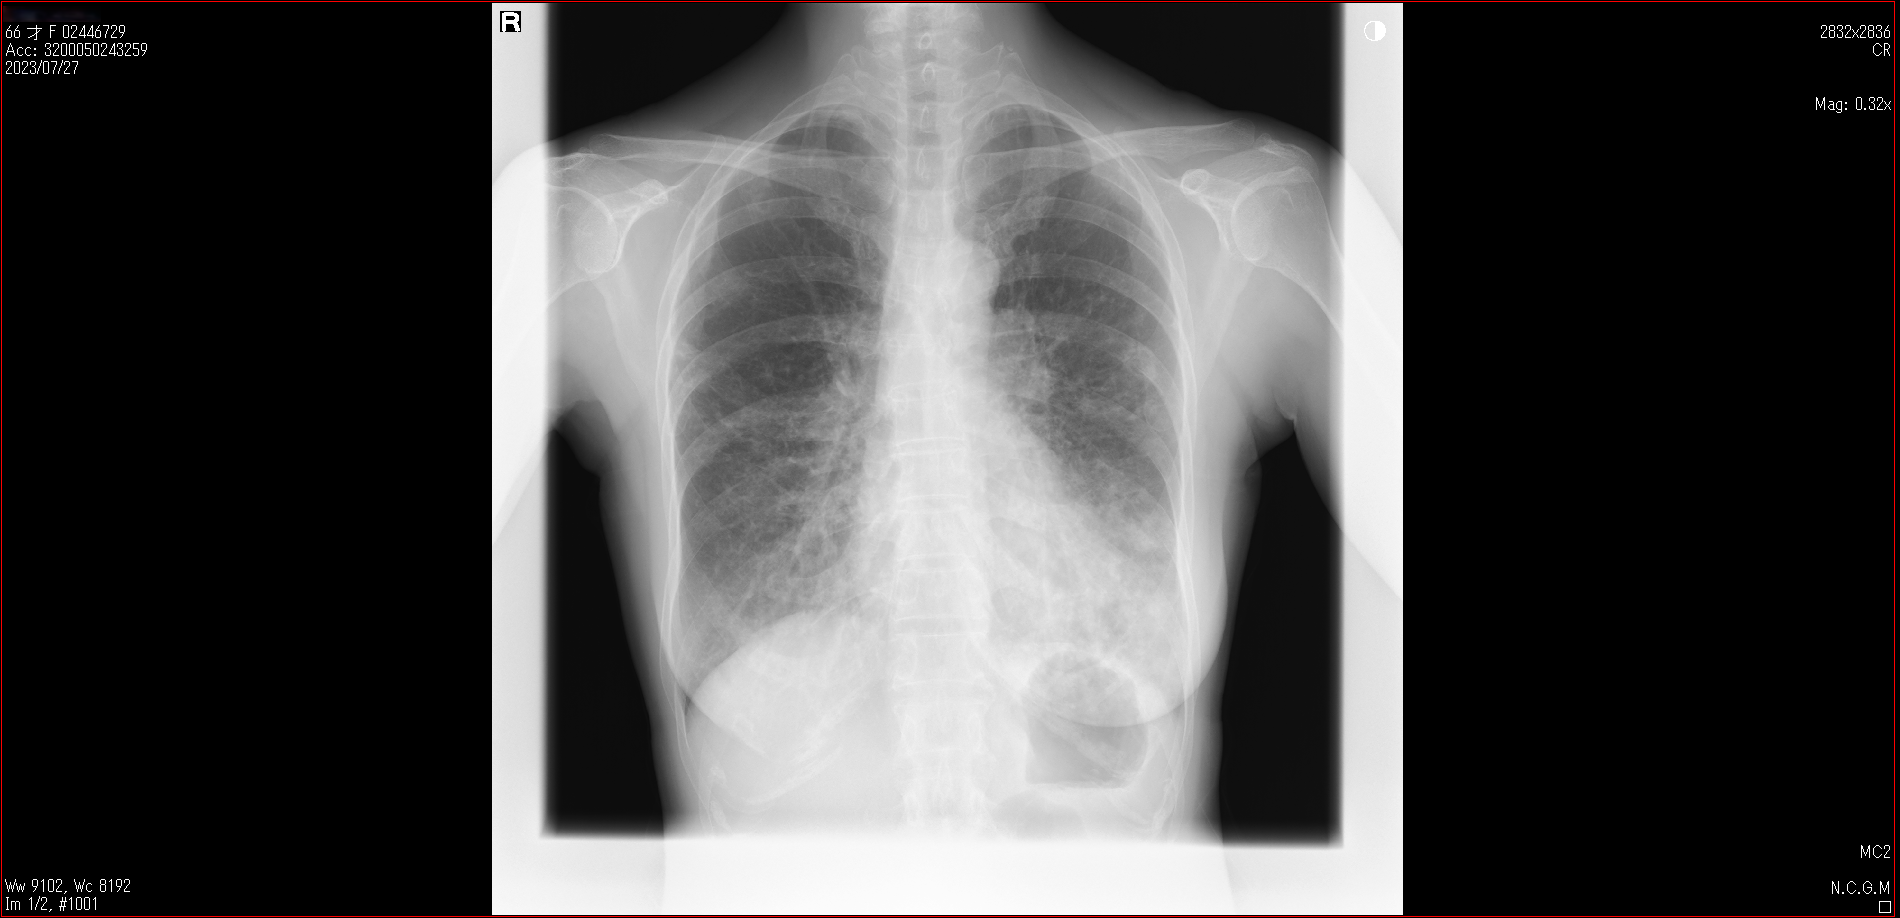

肺X線画像

- 2023.07.27 肺炎と診断された画像(国立系病院)